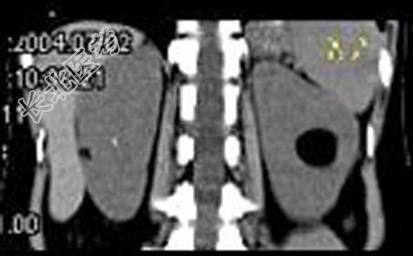

- 多项选择题女,38岁, 体检时B超在左肾探及一中强回声光团,边界清, 内部回声均匀,CT检查如图所示, 下列说法正确的是 ( )

A、左肾中部靠后方可见一类圆形低密度病灶

B、病灶与周围肾组织界限清楚

C、病灶密度为脂肪密度

D、考虑为左肾血管平滑肌脂肪瘤